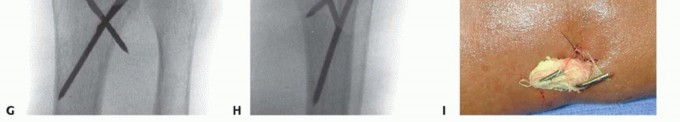

TECH FIG 4 • A. An incision is made over the second metacarpal base, with reflection of the first dorsal interosseous muscle and radial sensory nerve terminal branches. (The thumb is at the top of the photograph.) B. Diagram showing placement of fixator pins in the shaft of the index and the base of the index and long metacarpals. C. Parallel placement of two metacarpal pins. Proximal Pin Placement and Frame Construction

TECH FIG 5 • A. Incision over the radial forearm demonstrating the radial sensory nerve branch deep to the fascia. (The hand is to the right.) B. The double drill guide is placed onto the radius.(continued)

TECH FIG 5 •(continued)C. Final reduction is maintained by the addition of clamps and rods. D. K-wires are used for supplemental fixation when necessary.